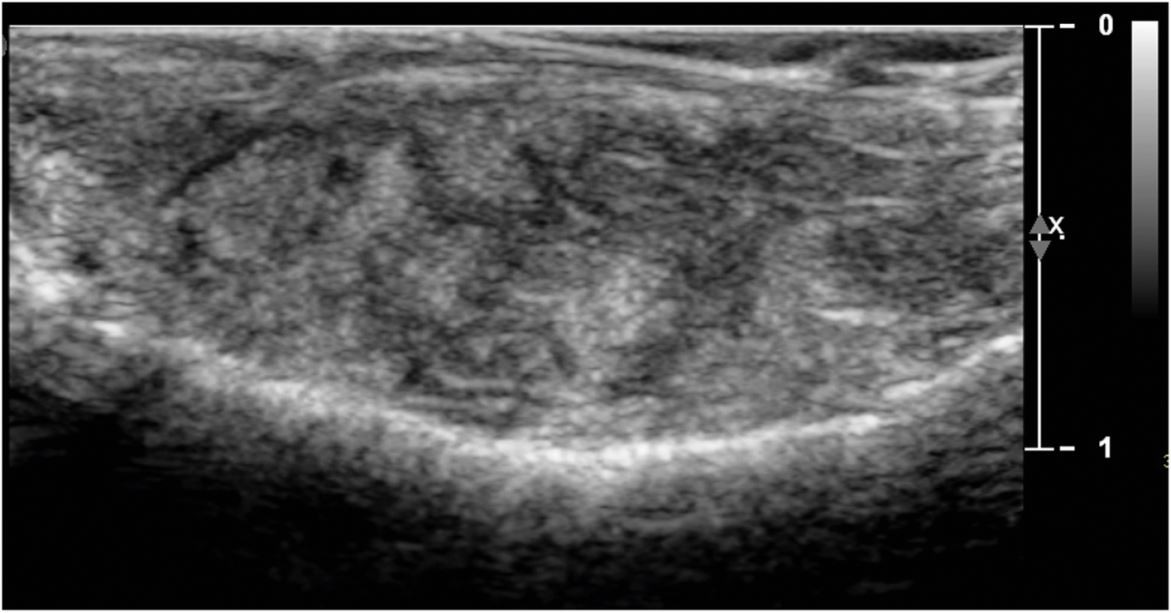

Fig. 4

Ultrasound of the palatal swelling. A solid tissue mass with minimal vascularity and no fluid collections or calcifications